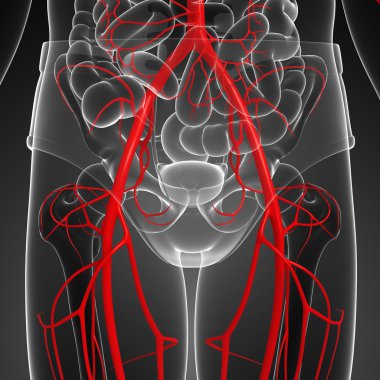

İdrar torbası anatomisi olan erkek idrar sistemi böbrekleri. 3d

ArkaplanGrafikselresimlemedizaynİzole edilmişkişiİnsaninsanlarSoyutSağlıksağlıklıİlaçerkekTıbbifasulyesiluetPankartgövdeHastalıkİçeridebiyolojiBilimkanserSistemAcıorgKasİskeletanatomiKas gücüx ışınıfizyolojiBöbrekTümöranatomikİdrar torbasıÜreterİdrarProstatÜretraÜrolojibilgi grafiği3B illüstrasyonnefronProstat bezinefrolojiBenzer İçerikler